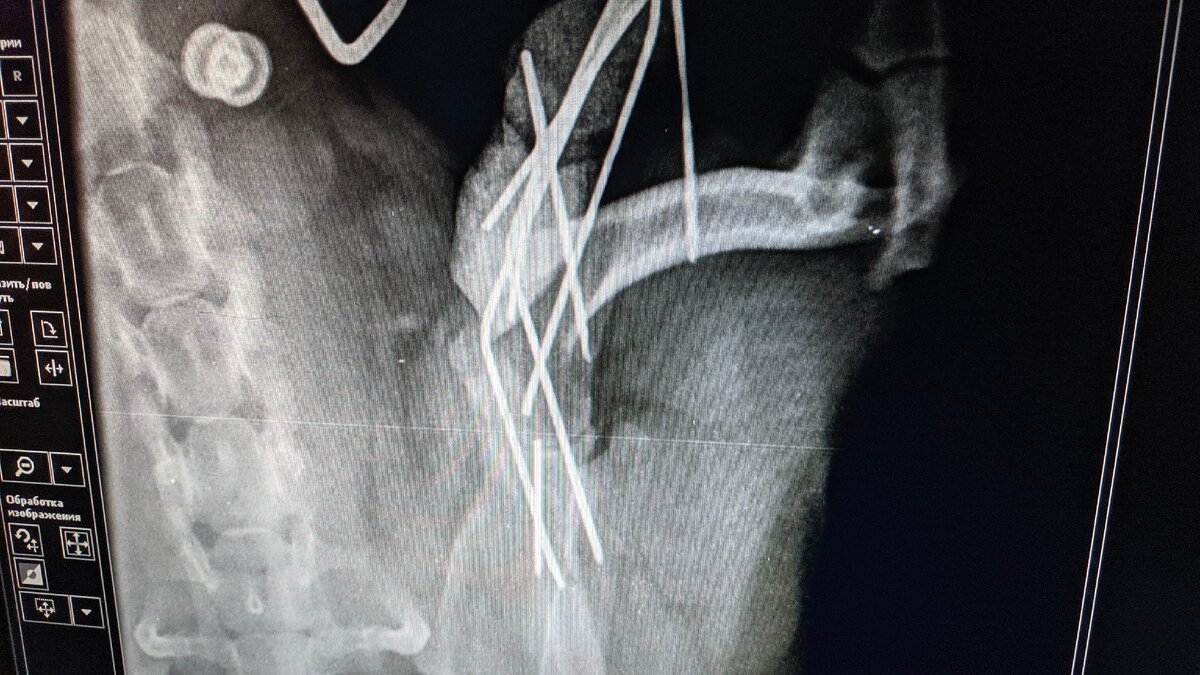

В декабре 2019 года случилась беда с моим пёселем, вывих плечевого сустава, лечили долго...первые полтора месяца лечили в нашем городе в частной клинике, было две операции, поставили спицы, которые она, через некоторое время, успешно сломала .

Всю эту конструкцию достали, кусок спицы остался - не решились доставать, очень тяжело было добраться, и он вроде бы не мешал ей, но на снимках было видно, что он находиться в миллиметре от сустава, что может привести , при случае, к неожиданным последствиям. *Специалиста* для проведения операции приглашали из другого города, так как местные спецы видимо не занимаются такими случаями...

Позвонили , записались на приём. Приехали , пёселя осмотрели, сделали рентген, как оказалось...то что ей делали в той ветеринарке, не делается вообще в таких случаях, так как этот метод бесполезен, сустав всё равно не держится после таких операций...такие вот *специалисты* работают в

некоторых клиниках.

Как видите разница в методах колоссальная)